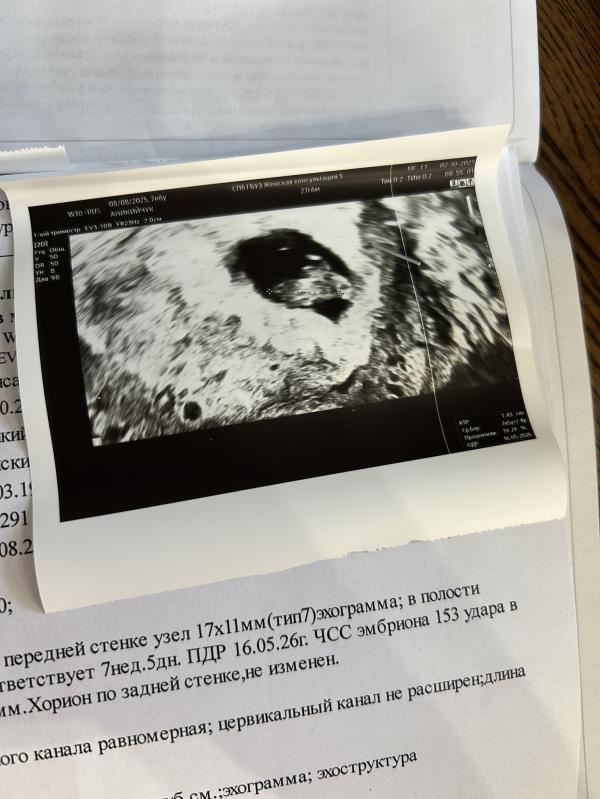

Растет мой малышок 🥹

Почти 1,5 см ктр